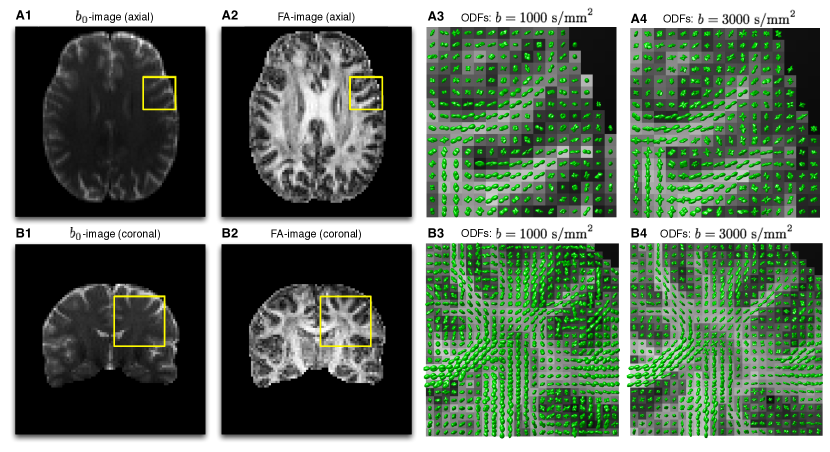

Additionally, real-life HARDI data were acquired by means of a 3T Siemens TrioTim MRI scanner. The diffusion-encoded scans were collected from a 45 y.o. healthy volunteer at 2 mm isotropic resolution with: s/mm2, TR=6300 ms, and TE = 85 ms. The transversal dimensions of the scans were equal to 128128 pixels, with a total of 50 axial slices used. The diffusion-encoding directions (with ) were defined using the method of generalized spirals [63], which provides a closed-form solution to the problem of quasi-uniform sampling of .

As the next step of our experimental study, real-life estimation has been performed using in vivo diffusion data (see Section 5.1). For the sake of the clarity of visualization, we restrict demonstration of the obtained reconstructions to 2-D views (aka “slices”), two examples of which are depicted in Fig 9. In particular, Subplots A1-A2 of the figure display an axial slice of the acquired -volume and its corresponding fractional anisotropy (FA) image, respectively, while Subplots B1-B2 show a coronal slice from the same 3-D volume along with its associated FA image, in the same order. Additionally, Subplots A3-A4 of Fig. 9 show the ODFs corresponding to the localized regions indicated by the yellow squares in Subplots A1-A2 for the case of s/mm2 and s/mm2, respectively. (To facilitate the analysis, the ODFs are shown over the background of their associated FA values.) Analogous results pertaining to the coronal view are shown in Subplots B3-B4 of the figure. It should be noted that, in both cases, the ODFs have been computed by means of the FRACT algorithm of [65], which seems to provide a reasonable balance between the robustness of more traditional QBI [25] and the high resolution gain of its solid-angle formulation [27].